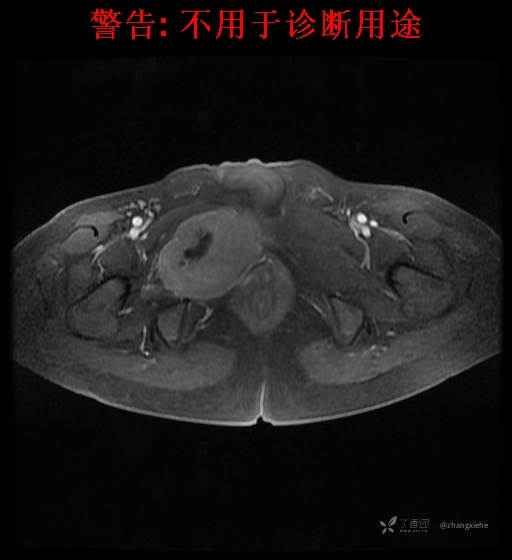

现病史:患者2022-02-07在市中医院体检发现右肺占位,胸部CT示:右肺下叶基底段见一不规则软组织密度影,增强扫描呈轻中度强化,可见血管贴边征。当时无任何不适。2022-02-24于省肿瘤医院行纤支镜检查阴性,痰检未找到癌细胞。经皮肺穿刺细胞学检查找到高度癌疑细胞,病理示:右下肺穿刺考虑神经内分泌癌。免疫组化结果:CgA(-)、CD56(-)、Syn(+)、CK广谱(-)、p40(-)、P63(少量+)、TTF-1(-)、Ki-67(+,40%)、NapsinA(-)、Calcitonin(-)、TG(-)。ECT示:全身骨扫描未见明确骨转移征象。患者出现贫血且逐渐加重、低蛋白血症,予人促红素注射液、精蛋白重组人胰岛素混合注射液、人血白蛋白对症处理,效果不明显,病情加重,右髋出现疼痛,不能行走。2022-03-04转院南大二附院进一步治疗,2022-03-20行右侧髂骨穿刺活检术,术后病理结果示:考虑软组织透明细胞肉瘤。免疫组化示:瘤细胞Vim(+)、NSE(+)、S-100(+)、SOX10弱(+)、Melan-A(+)、TFE-3部分弱(+)、CK(-)、MyoD1(-)、Desmin(-)、HMB45(-)、CD34(-)、CD68(-)、CR(-)、Ki-67约15%(+)。特殊染色示:网状纤维染色(-)、PAS(±)。

2022-03-05血常规示:血红蛋白:64g/L,生化示:白蛋白20g/L。骨髓涂片细胞学检查示:骨髓增生明显活跃,粒红比减低。粒、红、巨三系增生明显活跃。粒系伴成熟障碍。髓片浆细胞较易见,占7%。粒系增生明显活跃,核明显左移,可见巨幼样变及核浆发育不平衡。PET-CT示:1.右肺下叶软组织肿块、右侧耻骨下支及耻骨联合处骨质破坏伴软组织肿块形成,FDG代谢均异常增改,考虑恶性病变,建议病理检查;右侧髂血管旁、双侧腹股沟淋巴结反应性增生,建议随访。2.多浆膜腔(双侧胸腔、心包腔、盆腔)少量积液。3.全身骨骼FDG代谢弥漫增高,考虑骨髓反应性增生。4.大小肠条片状FDG代谢增高,考虑生理性摄取。5.右侧上颌窦面膜下囊肿,脑部FDG代谢未见明显异常。6.C7-T1层面后纵韧带钙化。患者乏力加重,卧床不起,不能承重,大小便不顺畅,转院至我院。门诊拟“1.右肺占位并右侧骨盆转移2.低蛋白血症3.中度贫血 4,血糖升高(原因待查)”收入住院。患者发病以来,无胸闷、胸痛,无呼吸困难,偶咳嗽,无咳血,饮食、睡眠欠佳,2个月之内体重减轻约10kg。